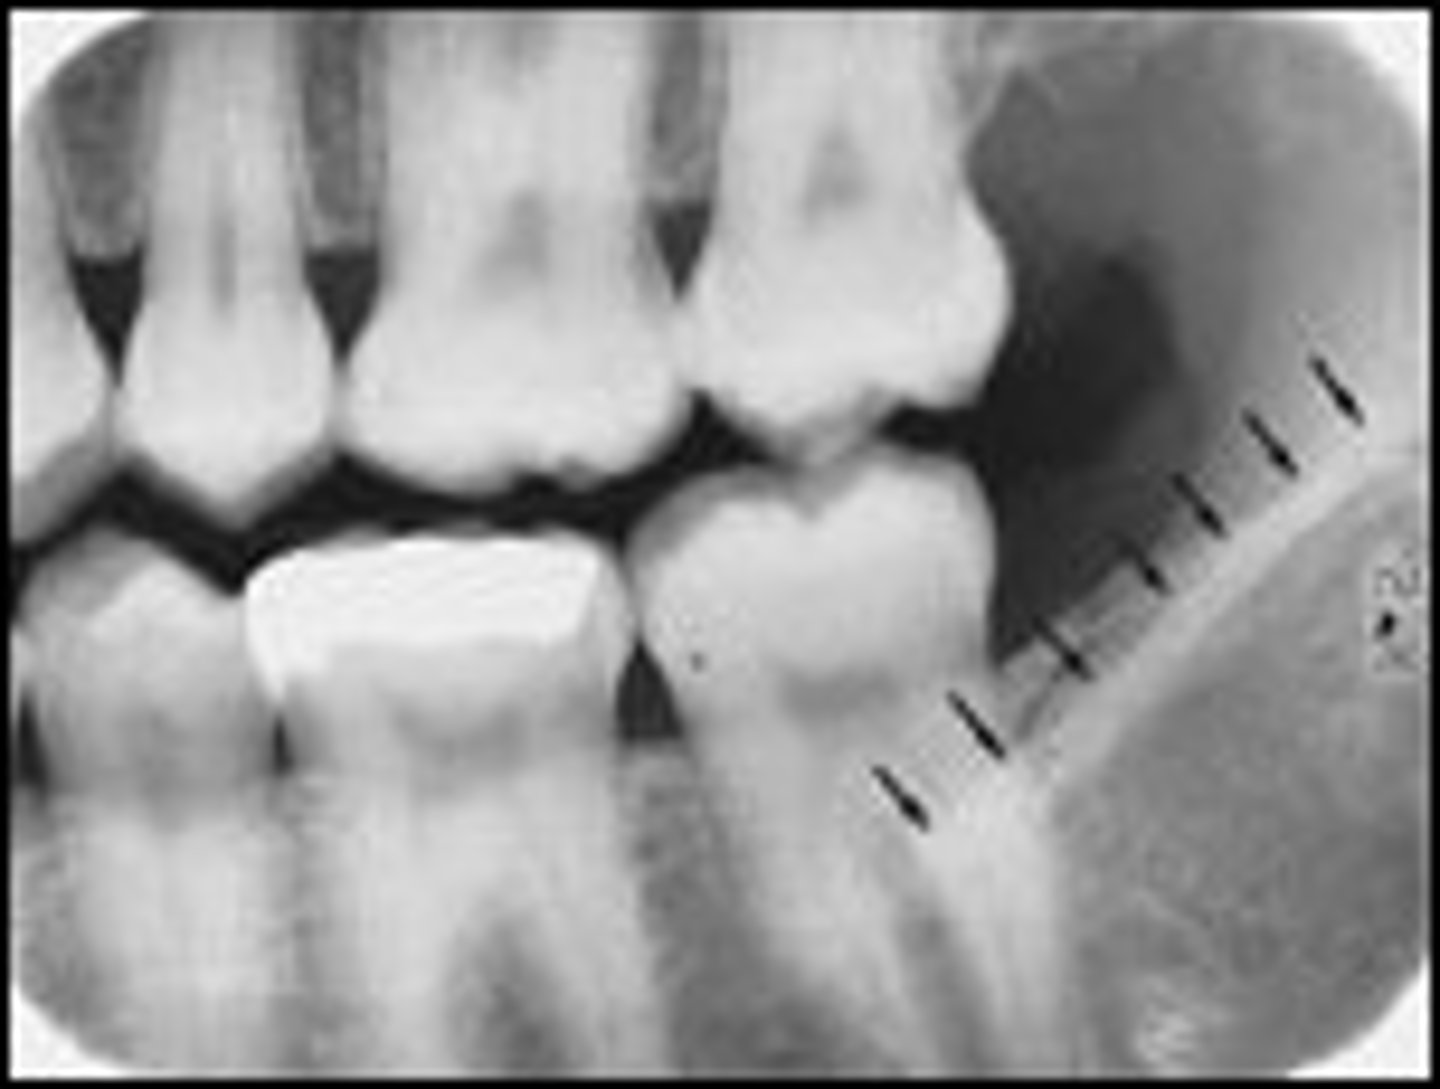

coronoid process of the mandible

bone seen on films taken in the far back of a pts mouth

radiopaque

hamular process

spike of bone seen behind the last molar

maxillary tuberosity

rounded portion of bone behind the last tooth